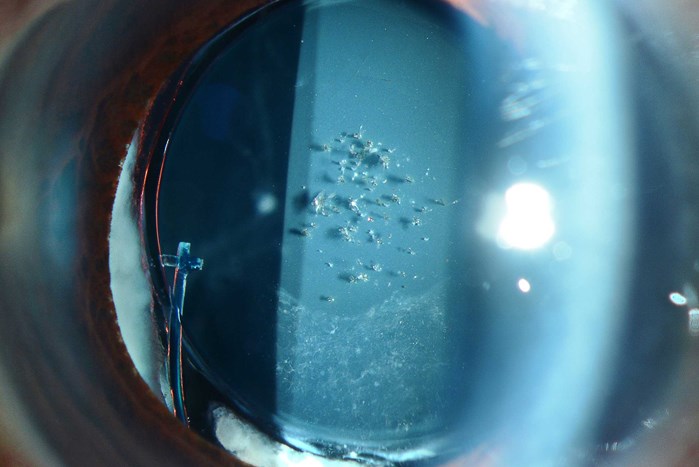

'Vitreous in the AC' by Robert Hancock, Specialist Ophthalmic Photographer, Wirral University Teaching Hospitals, UK.